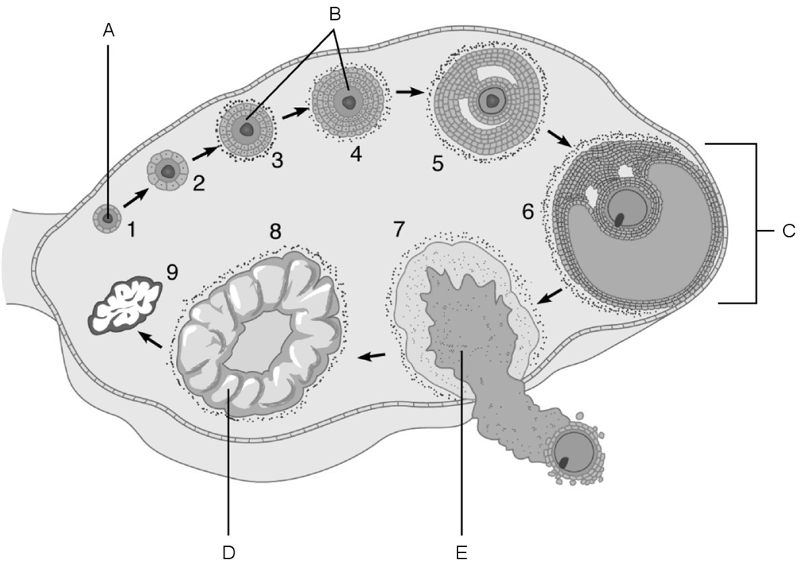

Afferent arteriole.

A

Cells that are most affected by ADH.

C

Cells that are the most active in reabsorbing the filtrate.

E

Medulla of the kidney.

E

Glomerulus.

C

Is composed of simple squamous epithelium.

A

Proximal convoluted tubule.

Site at which most of the tubular reabsorption occurs

Glomerulus.

Site of filtrate formation.

Peritubular capillaries.

Blood supply that directly receives substances from the tubular cells.

Collecting duct.

Site that drains distal convoluted tubule